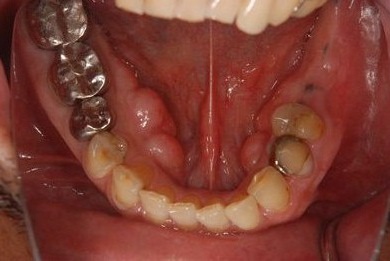

インプラントの症例写真 IMPLANT

インプラント治療

| 性別/年齢 | 男性 / 53歳 | ||||||||||||||||||||||||||||||||

| 主訴 | 左下奥歯2本のインプラント治療を希望。 | ||||||||||||||||||||||||||||||||

| 治療方針 | 左下欠損部分をインプラント治療にて機能的・審美的回復を行う。 | ||||||||||||||||||||||||||||||||

| 治療内容 | インプラント2本、ハイブリッドセラミッククラウン2本 | ||||||||||||||||||||||||||||||||

| 総治療費 | 399,000円 | ||||||||||||||||||||||||||||||||

| 治療期間 | 9ヶ月 |